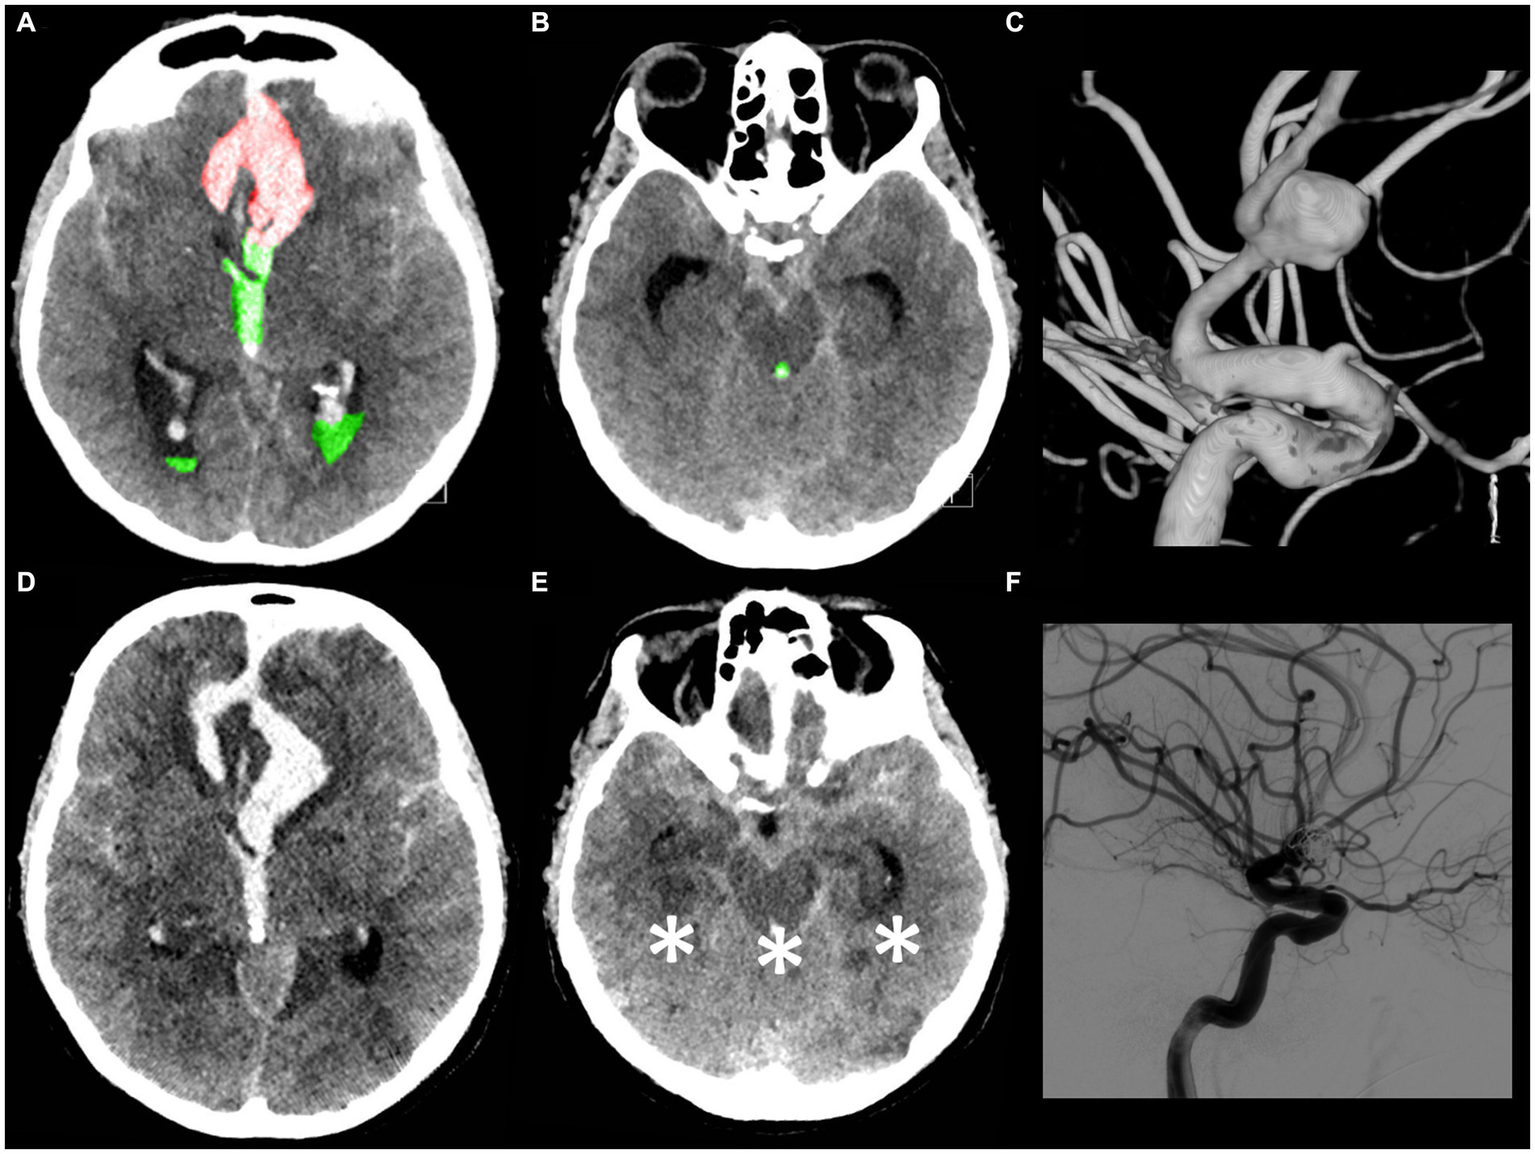

Figure 6

A 53-year-old male patient presented with a loss of consciousness. The WFNS score evaluation on admission was V with isochoric pupils and an intact pupillary light reflex. The initial CT scan (A,B) demonstrated the presence of a mFisher grade 4 aSAH with intraventricular hemorrhage (green A,B), volume 30 mL, and acute hydrocephalus with intraparenchymal hemorrhage (red A), volume 7 mL (IVH ratio 81%). The CT angiography and digital subtraction angiography (C) showed a ruptured communicating artery aneurysm. An urgent external ventricular drainage was placed and the aneurysm was endovascularly treated within 5 h of symptom onset. The 72 h post-treatment CT scan (D,E in corresponding slices as compared, respectively, with A,B) revealed the presence of bilateral temporal ischemia, occipital ischemia, and pontomesencephalic ischemia (asterisk E). (F) Post-coiling digital subtraction angiography showing aneurysm occlusion. The patient died 5 days after aSAH.